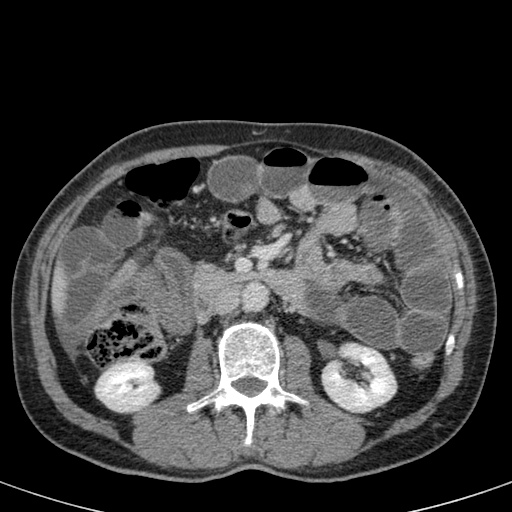

Ca lâm sàng bên trái cho thấy một bệnh nhân khác bị tắc ruột dạng quai kín.

Mặc dù các mạch máu ngấm thuốc tốt, nhưng dường như thành ruột không ngấm thuốc.

Các dấu hiệu thiếu máu cục bộ khác trong ca này bao gồm phù nề mạc treo và dày thành ruột.

Ruột bị nhồi máu được phát hiện trong quá trình phẫu thuật.

Nếu quai kín dài hơn và định hướng vuông góc với mặt phẳng cắt, chúng ta sẽ thấy một cụm quai ruột như trong ca lâm sàng bên trái.

Đôi khi điều này khó nhận biết chỉ trên các lát cắt ngang và các tái tạo mặt phẳng coronal hoặc sagittal có thể hữu ích.

Trong ca này, cũng có phù nề mạc treo và cổ